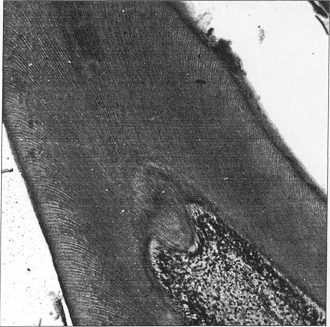

центральный слой - представлен рыхлой волокнистой тканью, содержащей фибробласты, макрофаги, более крупные кровеносные и лимфатические сосуды, пучки нервных волокон. (см. рис 1)

Рис 1. Пульпа зуба: ПС - периферический слой; НЗ - наружная (безъядерная) зона промежуточного слоя (слой Вейля); ВЗ - внутренняя (ядросодержащая зона промежуточного слоя; ЦС - центральный слой; ОБЛ - одонтобласты (тела клеток); КМС - комплексы межклеточных соединений; ООБЛ - отросток одонтобласта; ПД - предентин; КК -кровеносный капилляр; СНС - субодонтобластическое нервное сплетение (Рашкова); НВ - нервное волокно; НО - нервное окончание.